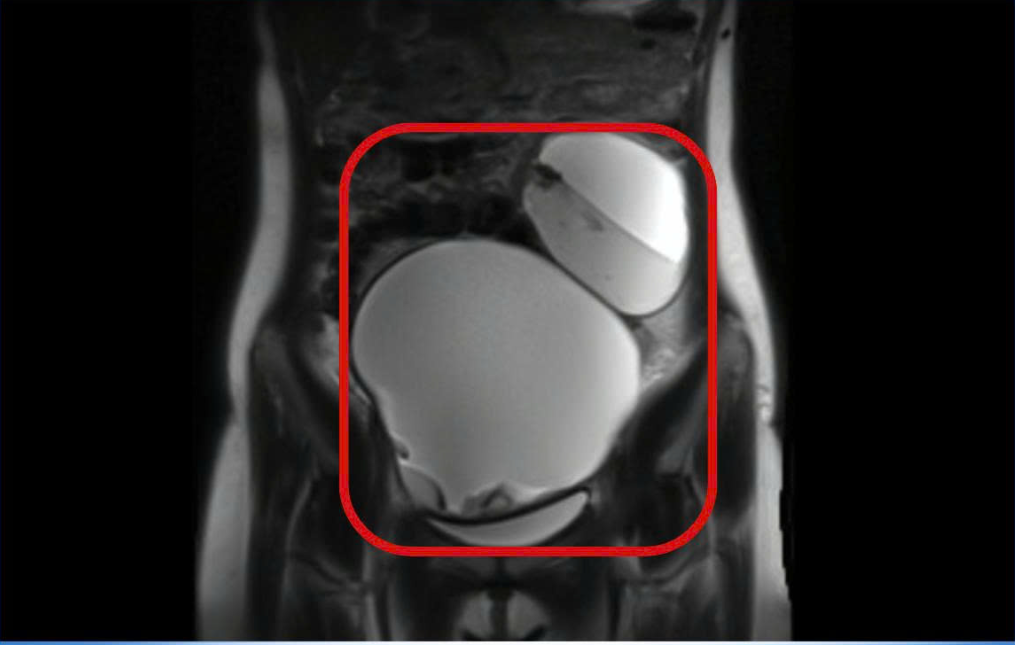

U buồng trứng 2 bên choán chỗ - Ảnh BVCC

Kết quả MRI cho thấy tử cung không bất thường, tuy nhiên hai buồng trứng đều có khối u choán chỗ. Khối u buồng trứng phải kích thước khoảng 13×15 cm, khối bên trái 8×10 cm, bên trong chứa dịch, mỡ và vôi hóa, ranh giới rõ.

Cả hai khối u đều bị xoắn – một biến chứng cấp cứu nguy hiểm. Chẩn đoán xác định u bì buồng trứng hai bên xoắn.